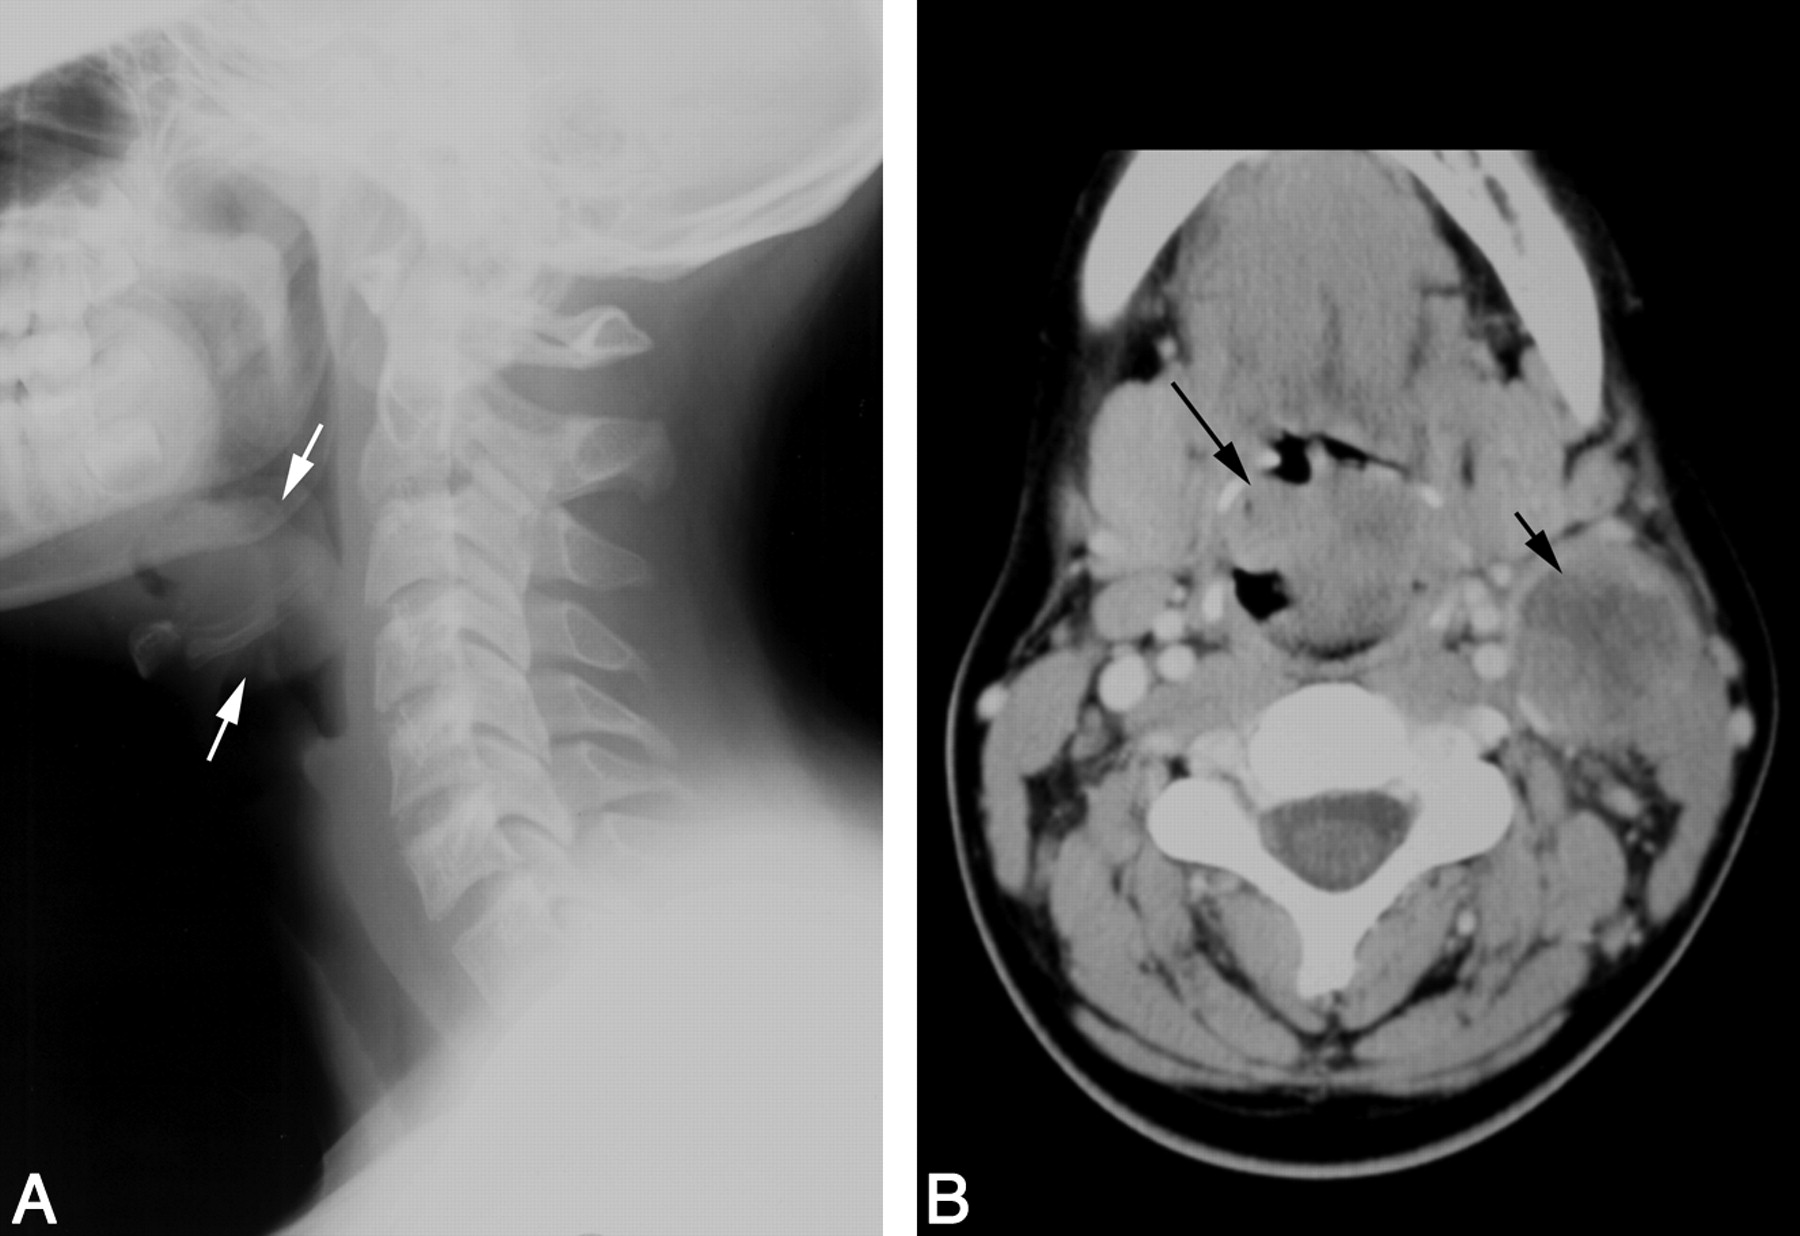

A lateral radiograph of the neck revealed a rounded, irregular mass in the region of the epiglottis (Fig 1A). Contrast-enhanced CT scan from the same institution revealed that the irregular, heterogeneously enhancing, 37-mm × 30-mm midline mass was arising from the epiglottis and aryepiglottic folds, extending into the hypopharynx, with significant narrowing of the airway. The tumor abutted the inner cortex of the hyoid bone. There was a conglomerate, heterogeneously enhancing necrotic mass of enlarged level II lymph nodes on the left, measuring 28 × 32 mm (Fig 1B). CT scan of the chest, abdomen, and pelvis revealed no metastatic disease.

Patient 1. Carcinoma of the epiglottis; t(15;19). A, Lateral film of the neck reveals an irregular epiglottic mass (arrows). B, Contrast-enhanced neck CT scan demonstrates the irregular, midline epiglottic mass (long arrow). There is necrotic left level II adenopathy (short arrow).